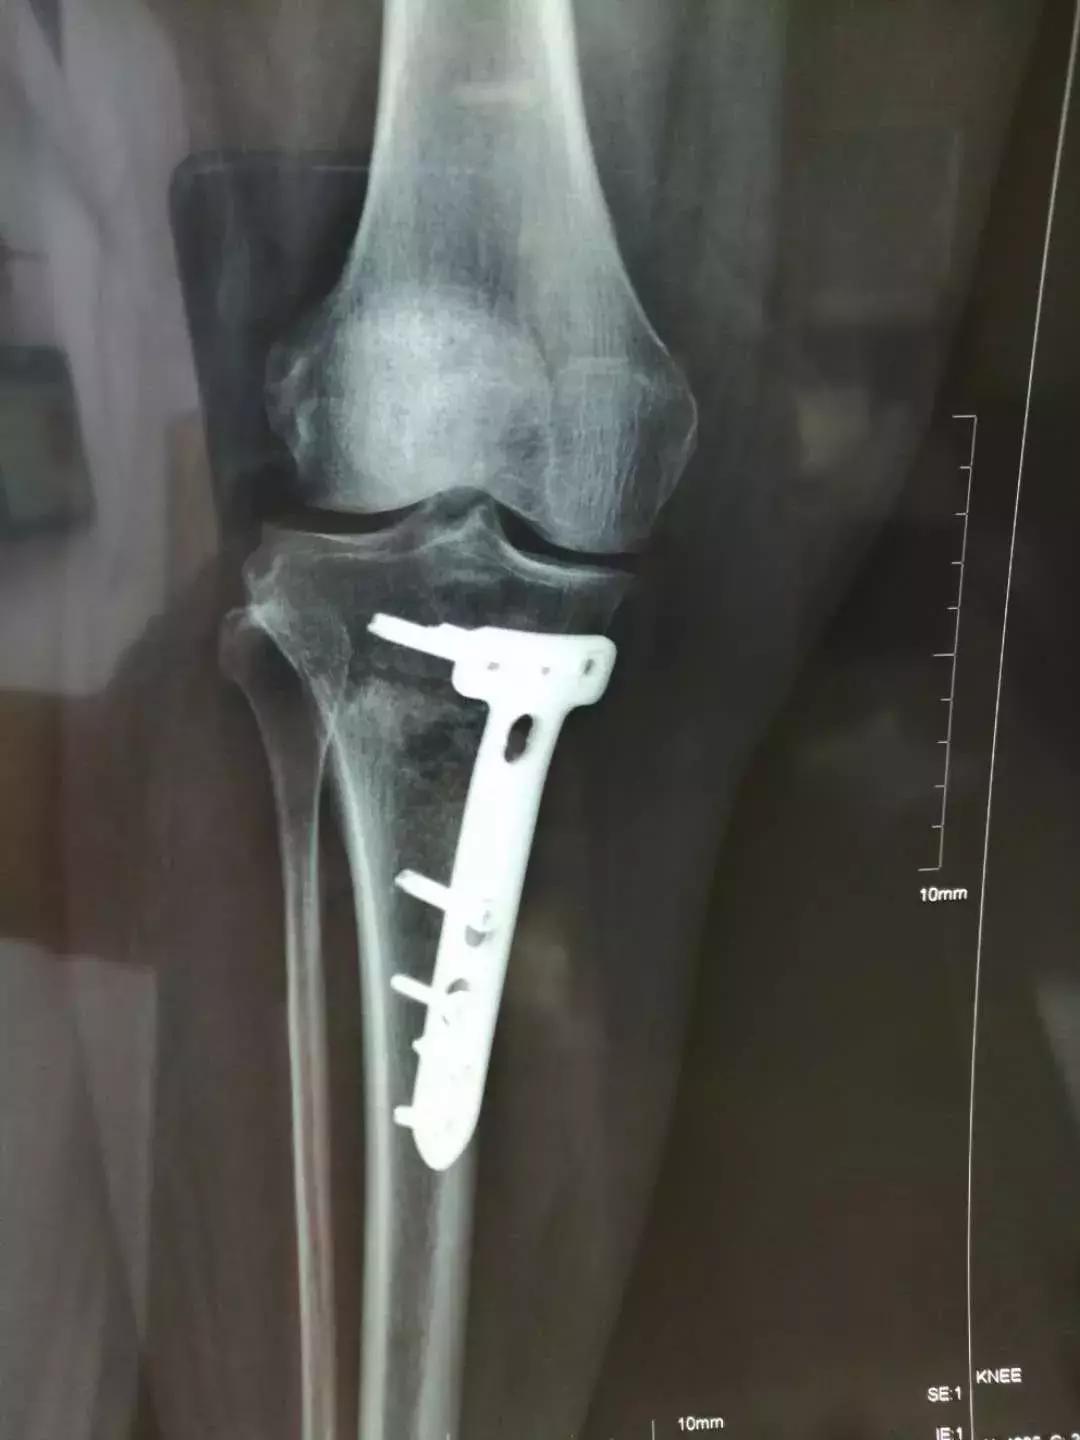

患者入院后,骨科医护人员根据患者身体症状,完善相关检查,在张云海博士的指导下,邱生海主任及闫煜军主管医师制定了精确而详细的手术方案及术后康复方案。25日,张云海博士为患者实施了HTO手术,骨科医护人员全程配合,手术用时2小时50分,进行顺利。矫正了患者膝关节内翻畸形,恢复了关节的正常力线及功能,缓解了疼痛症状。

术后第二天,患者下肢力线及膝关节功能均得到恢复,行走时膝关节疼痛症状症状明显缓解,逐步恢复正常生活。在保留自己的关节同时避免了关节置换,患者及家属非常满意。

太原人民医院骨科实施的首例HTO手术,填补了该项目的技术空白,可更好地为面临膝关节置换的患者提供诊疗和手术服务。据了解,相比于膝关节置换术,HTO手术创伤小,恢复快,保留了自然的膝关节。